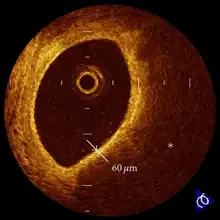

- ↑ Kubo, Takashi; Ino, Yasushi; Tanimoto, Takashi; Kitabata, Hironori; Tanaka, Atsushi; Akasaka, Takashi (2011). "Optical Coherence Tomography Imaging in Acute Coronary Syndromes". Cardiology Research and Practice. 2011: 312978. doi:10.4061/2011/312978. ISSN 2090-8016. Retrieved 10 November 2022.